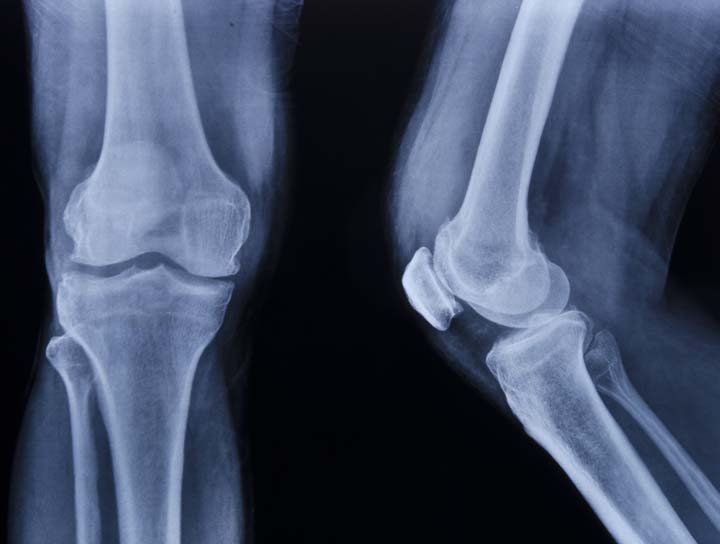

Osteoarthritis

Osteoarthritis is due to Wear and Tear of the cartilage.

With age our cartilage loses the resilience and undergoes degeneration.

Fractures or ligament injuries through the joint where the cartilage is also injured.

Infection of the joints